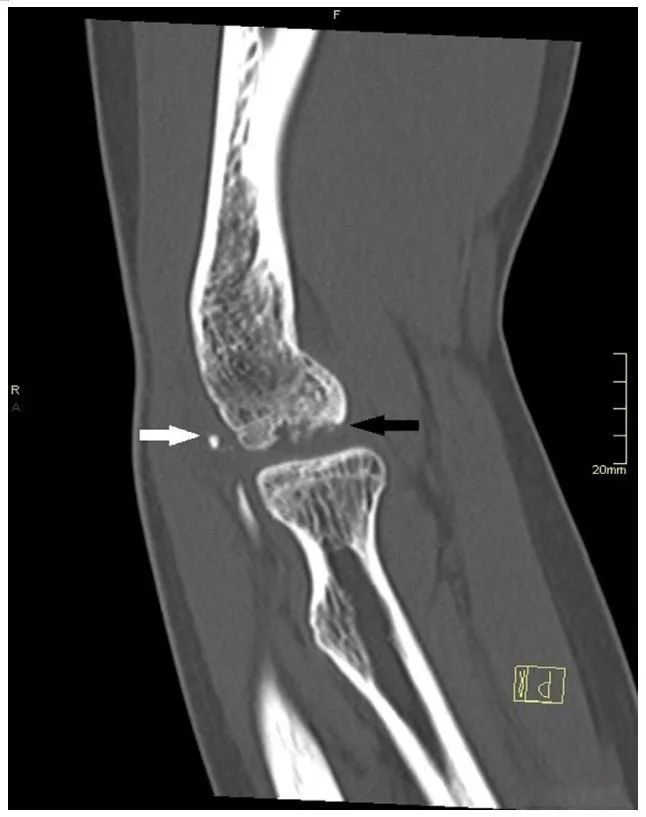

图五 一名 12 岁的肱骨小头剥脱性骨软骨炎患者 (黑色箭头) 的 CT 检查图像。我们发现,至少有 2 个关节内游离体位于肱骨小头 (白色箭头) 后方。

图五